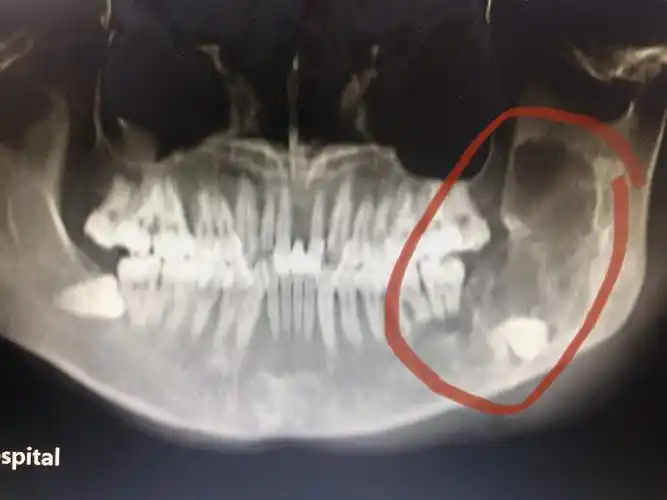

良性成牙骨质细胞瘤

于绵阳市当地医院就诊,曲面断层片示:左下颌牙瘤伴左下颌骨质异常增殖